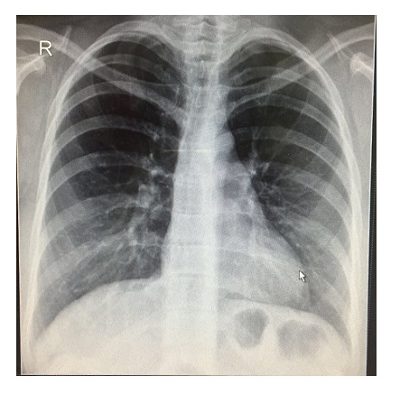

Что покажет расшифровка ФЛГ при пневмонии

Флюорография, показывающая пневмонию, насколько эффективным эта техника эффективна при определении заболевания? Действительно, фторграфия выявляет патологические изменения в структурах легких. Однако он не дает точного ответа, вызваны ли они раком, воспалением или инфекцией.

Следующие симптомы считаются рентгенологическими симптомами пневмонии:

- Фокусное воспаление на поверхности легочной ткани;

- Сегментированное утолщение;

- повышенная тяжесть сосудистых симптомов;

- Наличие экссудата в плевральной полости;

- Увеличенные грунтовые лимфатические узлы;

- Фиброзное изменение как следствие воспаления легких.

Как правило, флюорография показывает несколько признаков патологии, которые следует оценивать в целом, учитывая интенсивность и возможные причины развития.

При наличии такого заболевания в виде пневмонии в картинках видно многочисленные уплотнения в нижних сегментах легких.

Опытный и квалифицированный врач сможет отличить массу от рака. Опухоли Atype характеризуются размытым ходом и асимметричными.

Если инфильтрация в легких находится за тенью сердца, доктор заказывает производительность рентгеновского фото в двух прогнозах.